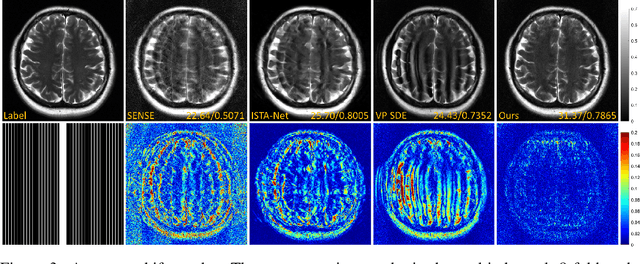

Abstract:Denoising diffusion probabilistic models (DDPMs) have been shown to have superior performances in MRI reconstruction. From the perspective of continuous stochastic differential equations (SDEs), the reverse process of DDPM can be seen as maximizing the energy of the reconstructed MR image, leading to SDE sequence divergence. For this reason, a modified high-frequency DDPM model is proposed for MRI reconstruction. From its continuous SDE viewpoint, termed high-frequency space SDE (HFS-SDE), the energy concentrated low-frequency part of the MR image is no longer amplified, and the diffusion process focuses more on acquiring high-frequency prior information. It not only improves the stability of the diffusion model but also provides the possibility of better recovery of high-frequency details. Experiments on the publicly fastMRI dataset show that our proposed HFS-SDE outperforms the DDPM-driven VP-SDE, supervised deep learning methods and traditional parallel imaging methods in terms of stability and reconstruction accuracy.